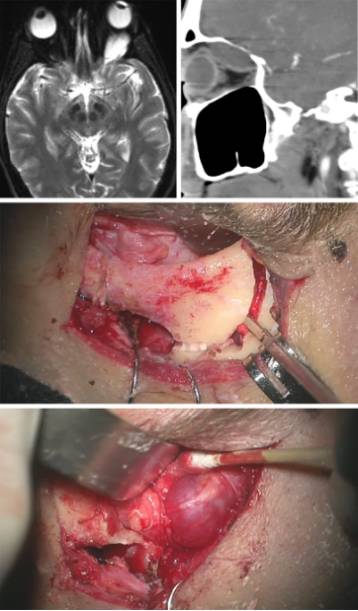

图6. 通过眶上入路单瓣眶壁截骨(中图)切除位于眼眶上部并导致突眼的神经鞘瘤。注意肿瘤表面的神经起源(底图)。